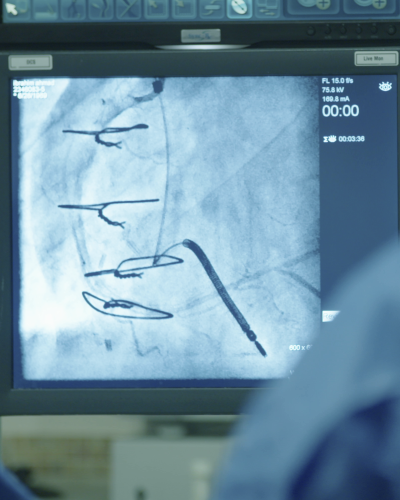

Cardiac catheterization is a minimally invasive procedure used to diagnose and treat various heart conditions. During the procedure, a thin, flexible tube known as a catheter is inserted into a blood vessel in the arm or leg and guided to the heart. This allows your provider to measure blood pressure within the heart chambers, assess the function of the heart valves, and obtain images of the coronary arteries using contrast dye and X-ray technology, such as fluoroscopy.

Cardiac catheterization plays a crucial role in identifying blockages in the arteries, which can lead to conditions like coronary artery disease. Depending on the findings during the procedure, therapeutic interventions such as balloon angioplasty or stent placement may be performed to restore adequate blood flow to the heart muscle.

Cardiac catheterization offers numerous benefits that enhance the diagnosis and treatment of heart conditions. One of the primary advantages is its ability to provide real-time imaging of the heart and coronary arteries, allowing your provider to evaluate the severity and location of blockages with precision. This targeted approach enables early and accurate diagnosis, which is crucial for effective treatment planning.